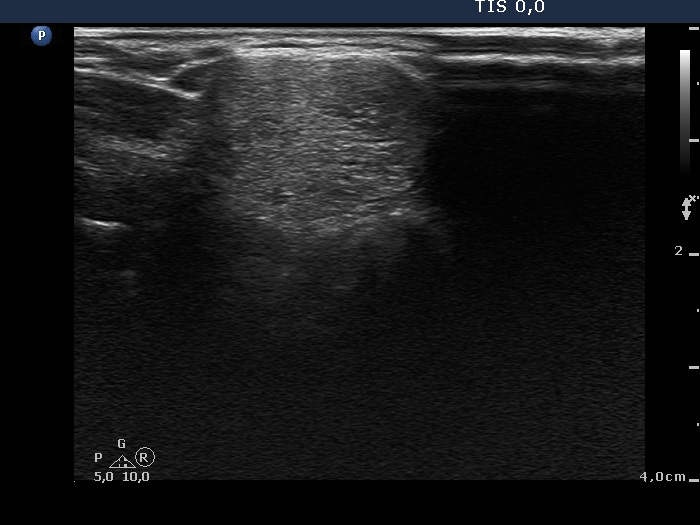

Ultrasonography. The thyroid was echonormal. There were multiple moderately hypoechogenic nodules in the right lobe making the appearance micronodular. There was a relatively larger hyperechogenic nodule in the isthmus. The left lobe contained a hypoechogenic lesion, which presented blurred borders, microcalcifications and an increase intranodular blood flow.